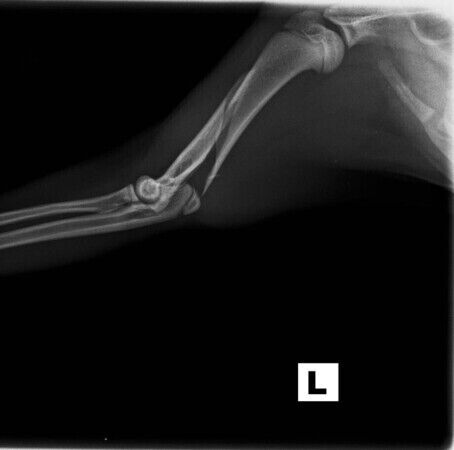

Leider hat sich Willi kürzlich eine Oberarmfraktur zugezogen. Der Tierarzt musste den kleinen Kerl umgehend operieren: die OP hat 976,79 EUR gekostet. Bitte helft uns, diese hohen OP-Kosten für Willi und viele, weitere Intensivpatienten zu decken.